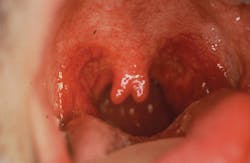

It has been suggested that the uvula is instrumental in directing the mucous secretions that drain from the nasal cavity to the back of the tongue. Other purposes include protection from the eustachian tubes, immunological functions, protection of the throat from hot foods and liquids, and encouraging proper direction of solid foods. We have known about the bifid uvula in connection with cleft palate cases for some time, yet some authors have reported no known functions for the uvula in decades past (figure 1).1,2